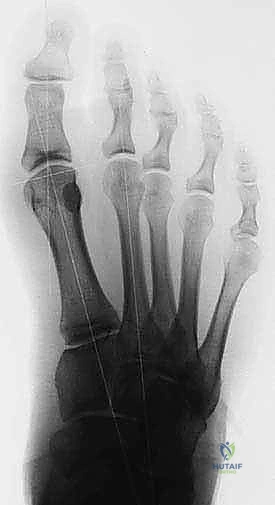

Figure 3: Anteroposterior view of a foot demonstrating a classic bipartite tibial sesamoid.

Figure 3: Another AP view of a bipartite sesamoid.

- Ossification and Variations: Ossification typically occurs from multiple centers between ages seven and ten. This developmental process accounts for the relatively common finding of bipartite (two segments) or tripartite (three segments) sesamoids, with the tibial sesamoid being bipartite in about 19% of the population and bilateral in 25% of patients. This anatomical variation often complicates diagnosis, as differentiating a congenital bipartite sesamoid from an acute fracture can be challenging.

FIG 10 • Preoperative ( A ) and postoperative ( B ) standing radiographs of the foot showing no change in the clinical alignment of the metatarsophalangeal joint after tibial sesamoidectomy. (From Lee S. Technique of isolated tibial sesamoidectomy. Techn Foot Ankle Surg 2004;3:85–90, with permission.)